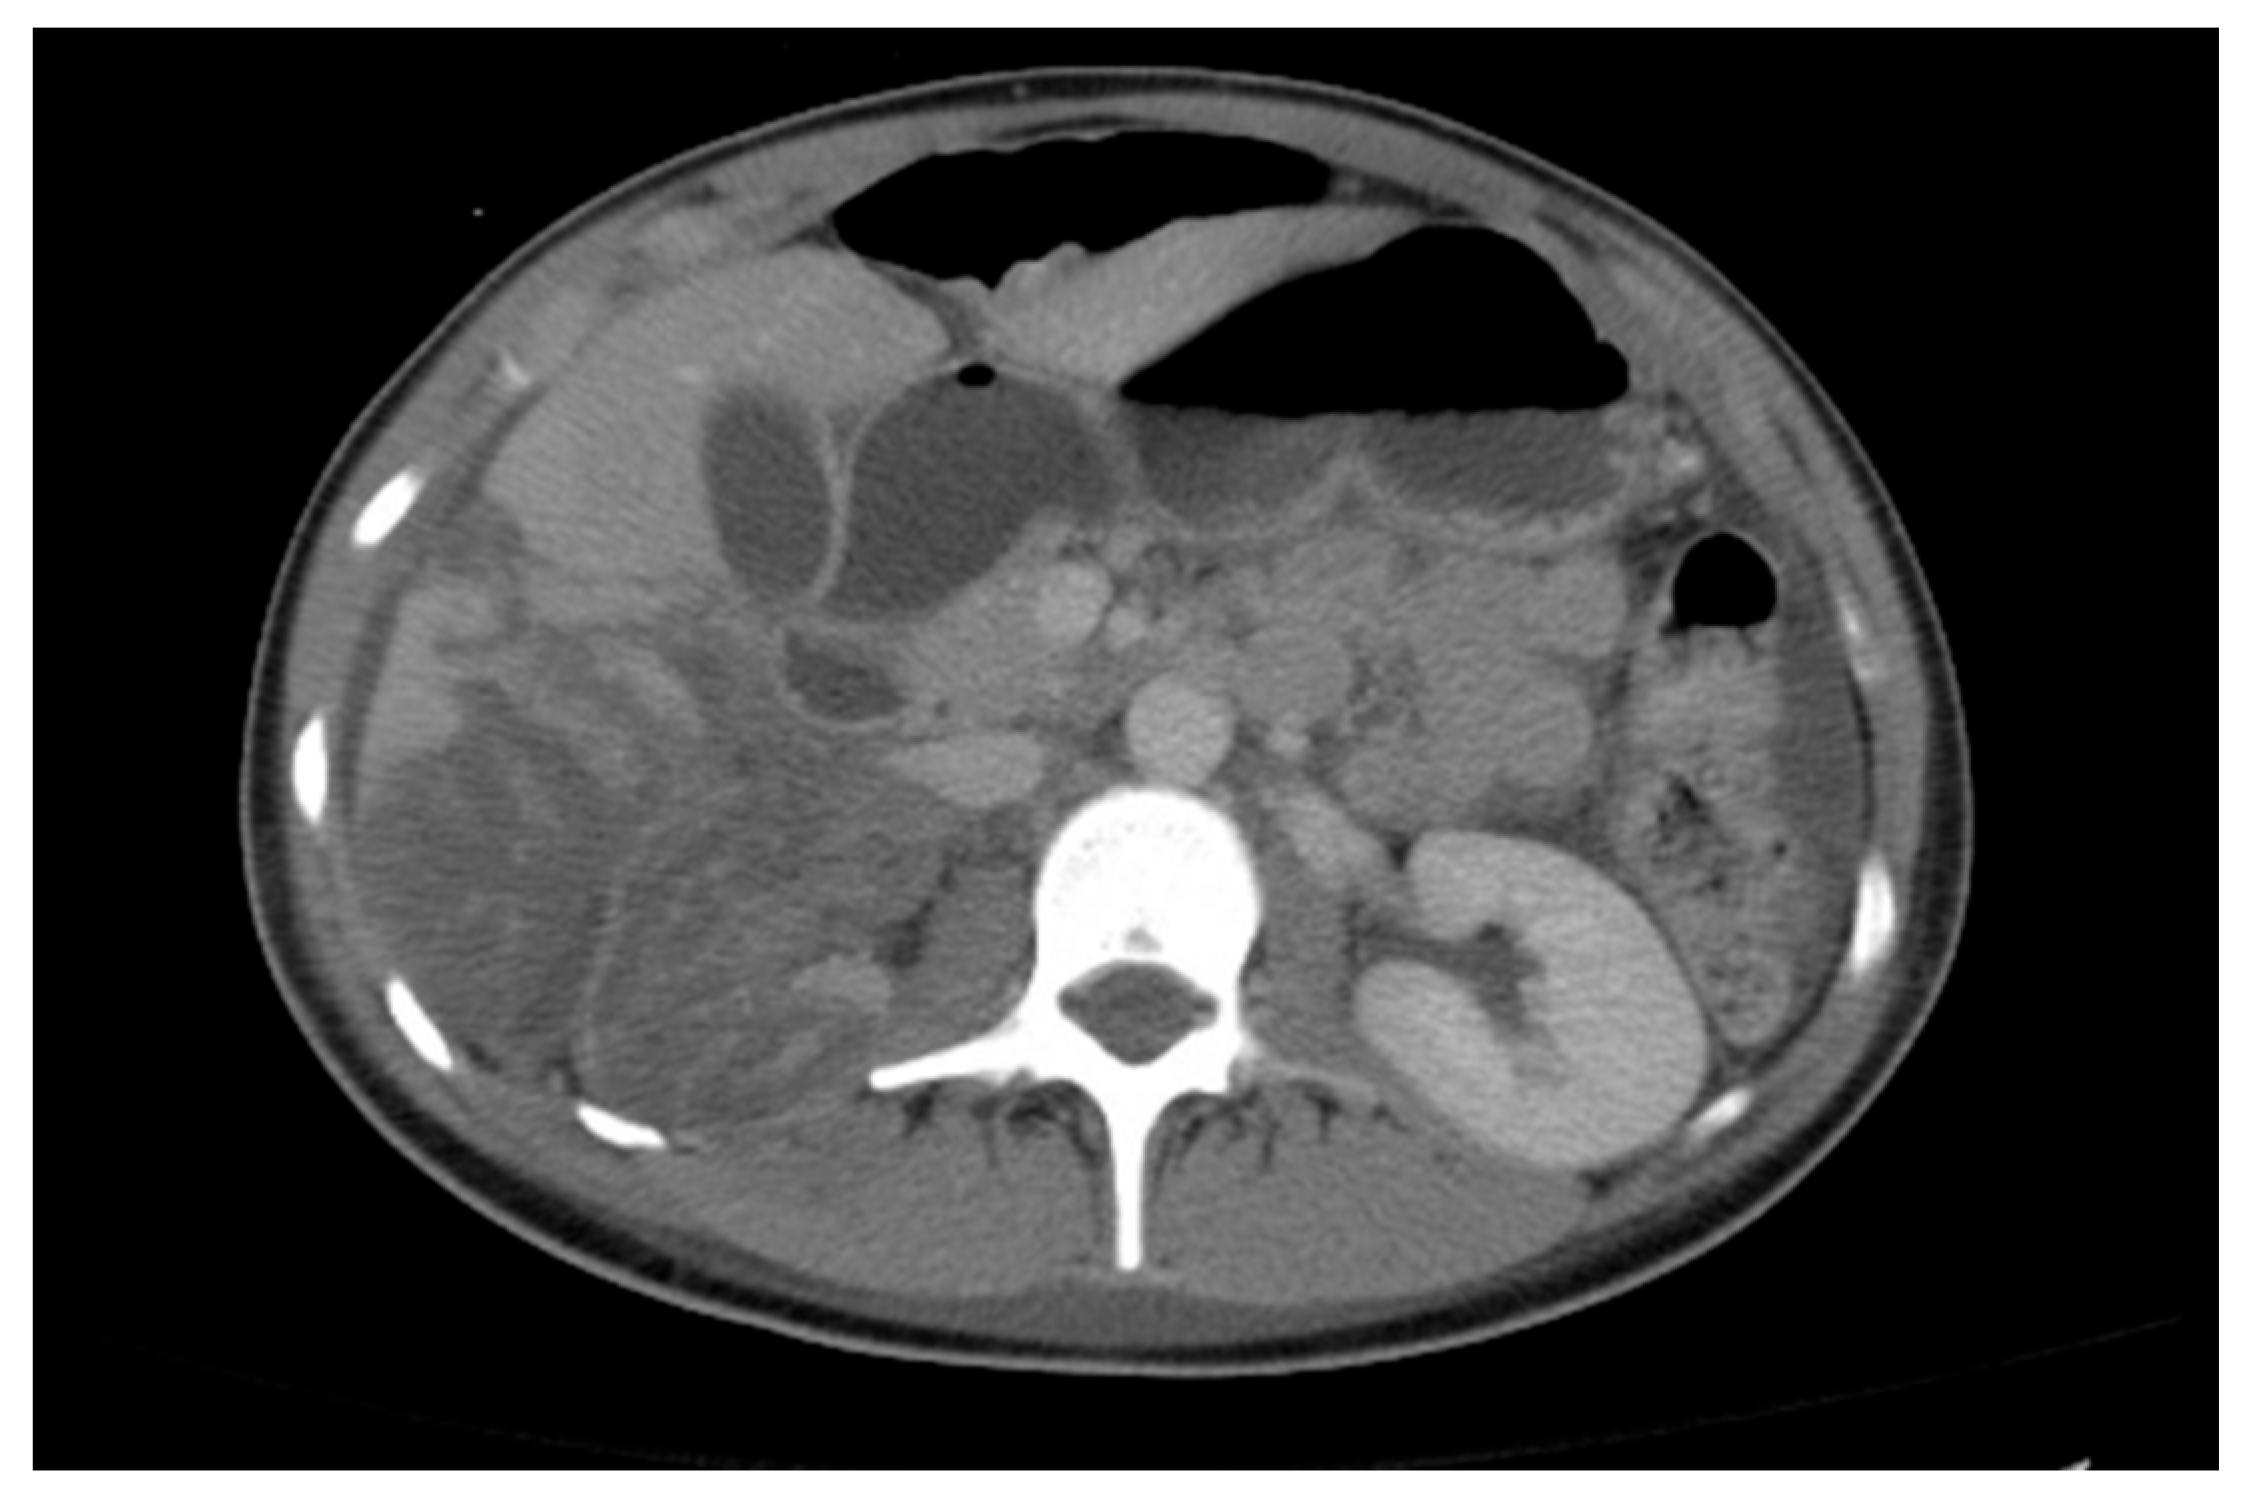

Obstruction at the ureteropelvic junction (UPJ) is a common congenital urinary tract obstruction. It is often diagnosed via antenatal ultrasound (US), which can reveal significant pelvic and calyceal dilation. Postnatally, UPJ obstruction can be detected using US, CT, or MRI, but dynamic nuclear medicine remains the gold standard for diagnosis (Figure 10 and Figure 11).

Figure 11. CT scan showing left ureteropelvic junction obstruction.

Medicina 61 00696 g011